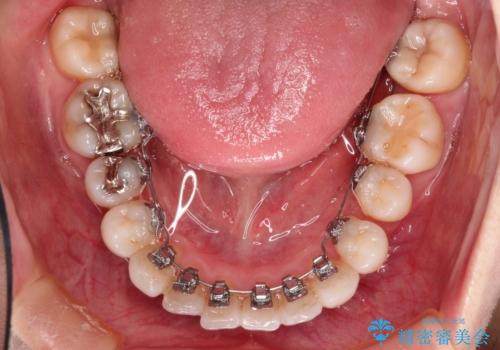

- リンガル

上下裏側矯正であったため、舌に傷や口内炎ができるなどつらい経験もされましたが、目立たずに治療できたことに喜んでいただけました。